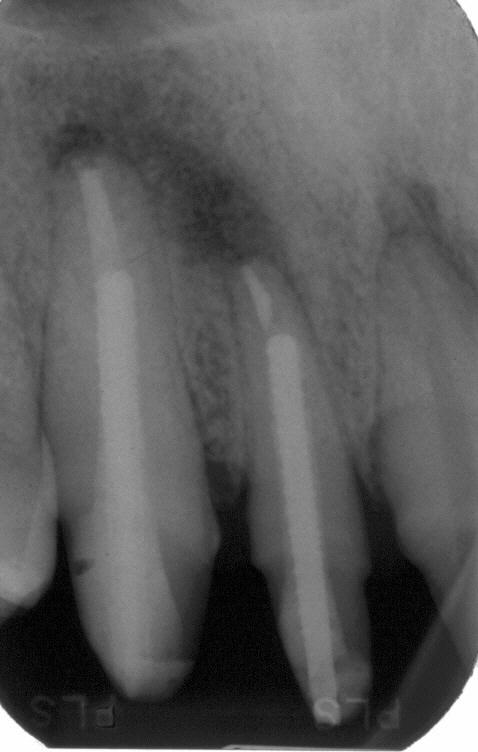

Zustand nach adhäsiver Insertion

Zustand nach adhäsiver Insertion eines Titanstiftes im Januar 1997 also neun Monate nach Wurzelfüllung unmittelbar vor Eingliederung eines Langzeitprovisoriums. Die Ausheilungstendenz auf nur konservativem Wege ist deutlich sichtbar

Langzeitkontrolle

Langzeitkontrolle vor definitivem Zahnersatz im April 1998. Die Ausheilung scheint im Vergleich zum vorherigen Bild nicht weiter voranzuschreiten